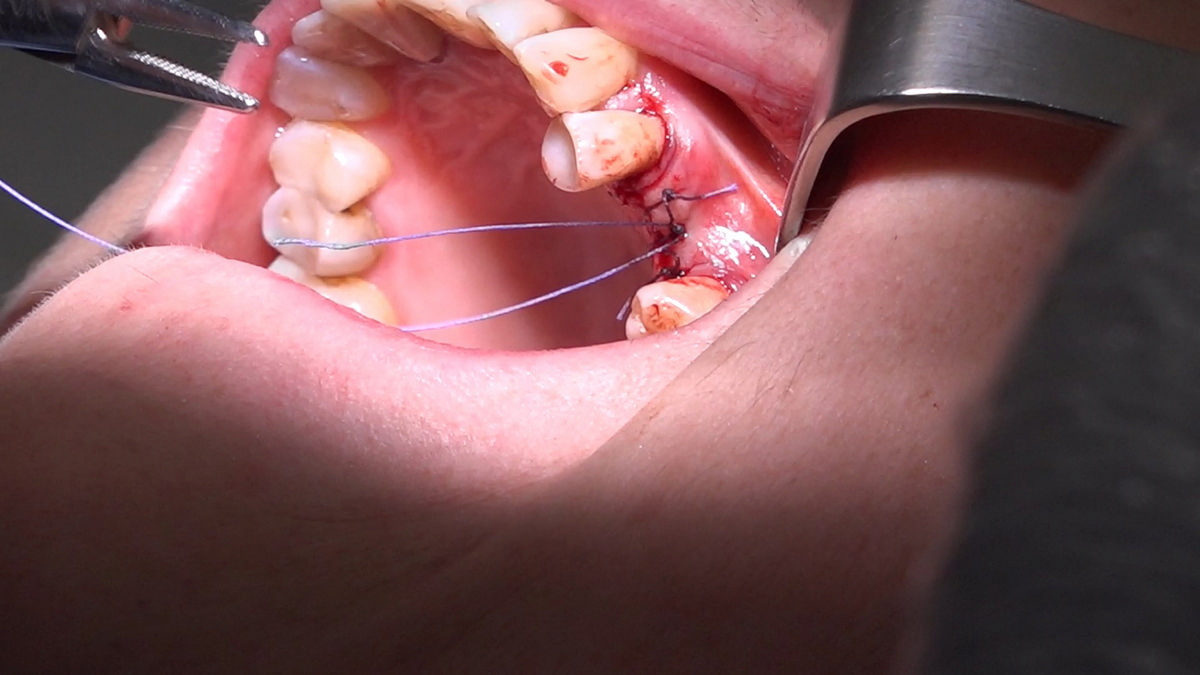

PRACTICULUM IMPLANTOLOGII - SEZON X - SESJA 4 - GRUPA B